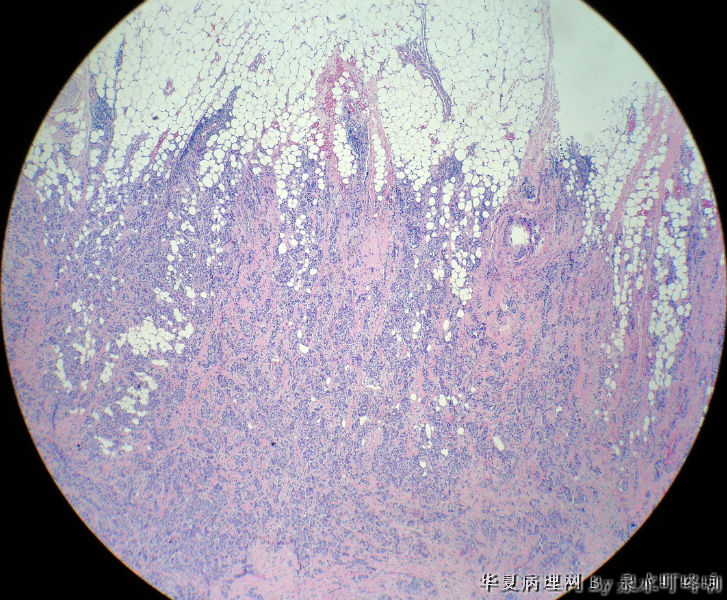

右腋下包块

女,60岁,右腋下肿物两年余。

大体:灰白带皮组织一块,大小约3.8×2.2×1.4厘米,皮肤呈橘皮样改变,切面灰白,质韧。

乳腺浸润型导管癌(副乳起源?还是原发灶在乳腺,腋下为癌结节?)

首先考虑 乳腺浸润性导管癌 转移,建议进一步免疫组化(CK7、CK20、ER、PR)确诊。

乳腺来源的浸润性导管癌,至于是乳腺癌转移而来还是副乳发生,应该结合临床病史和其他检查结果来综合判定,不是单纯依靠病理切片可以判断的。

皮肤转移癌 脉管内见栓 考虑来自乳腺